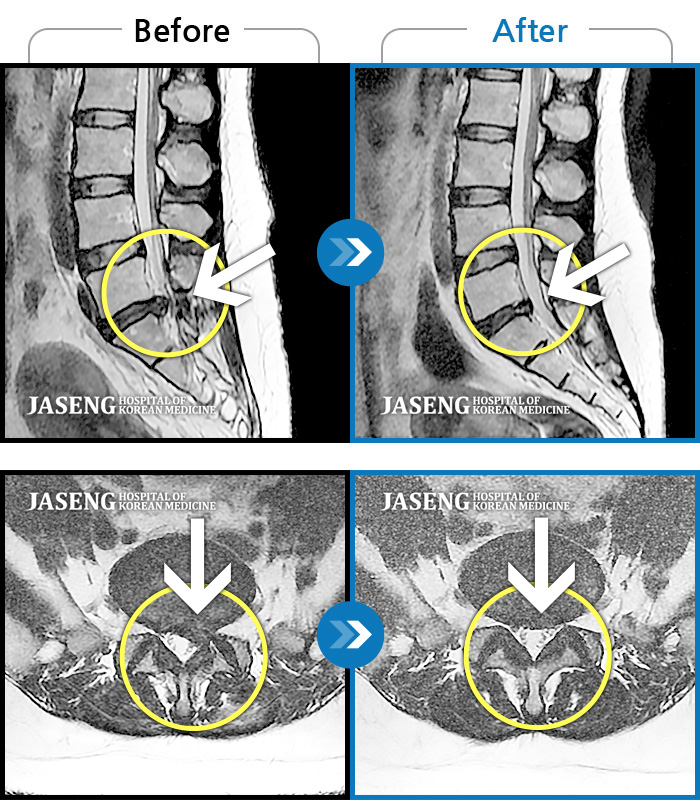

허리디스크

일산 · 김태용 원장

허리와 우측다리가 심하게 저렸다.

촬영시기

2020.05.07 ~ 2020.12.29

2021.02.26

조회수 125